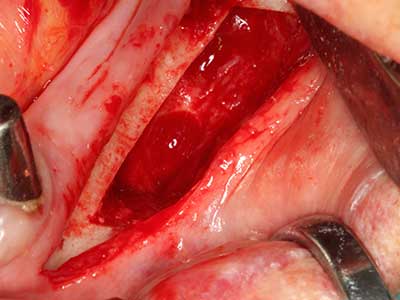

Sollen chirurgische Eingriffe mit unmittelbarer Knochenbeziehung an empfindlichen Strukturen wie Blutgefäßen oder Nerven erfolgen, so bergen rotierende Instrumente ein erhebliches Potential an iatrogener Schädigung. Gerade bei Nervdarstellungen nach iatrogener Schädigung, oder aber im Zuge einer Nervlateralisation für resektive und rekonstruktive Eingriffe oder Implantatinsertionen können piezoelektronische Geräte hilfreich sein Knochendeckel zu präparieren und nervnahe Hartgewebsanteile zu entfernen (Abb. 17-20). Ein leichter Kontakt des Nervstrangs zur Piezospitze bleibt dabei in der Regel folgenlos – allerdings kann eine unvorsichtige Vorgehensweise mit sägeartigen Bewegungen bzw. Ansätzen bei noch vorhandener knöcherner Unterlage durchaus temporäre oder aber auch permanente Nervschädigungen verursachen. Das Risiko einer solchen Schädigung wird jedoch als wesentliche geringer eingeschätzt als unter Anwendung von Säge- oder Fräsinstrumenten (Pereira, Gealh et al. 2014).

Wie sich in der Vergangenheit gezeigt hat stellt prinzipiell jeder knochenchirurgische Eingriff eine mögliche Indikation für die Piezochirurgie dar. So lässt sich die Präparation des mobilen Segmentes bei der Distraktionsosteogenese (Abb. 23-25) und der Sandwichosteotomie mit speziellen Ansätzen bewerkstelligen, ohne die für den Erfolg beider Techniken essenzielle Blutversorgung des krestalen Anteils zu gefährden (Gonzalez-Garcia, Diniz-Freitas et al. 2008).